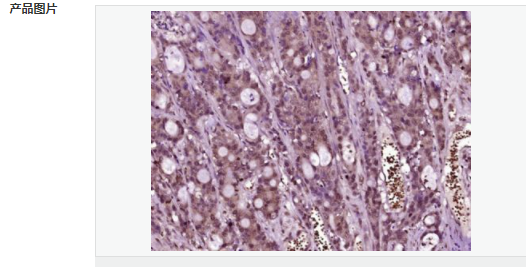

| 產品應用 | ELISA=1:5000-10000 IHC-P=1:100-500 IHC-F=1:100-500 Flow-Cyt=1μg/Test ICC=1:100 IF=1:100-500 (石蠟切片需做抗原修復) not yet tested in other applications. optimal dilutions/concentrations should be determined by the end user. |

| 產品介紹 | Ki67 antigen is the prototypic cell cycle related nuclear protein, expressed by proliferating cells in all phases of the active cell cycle (G1, S, G2 and M phase). It is absent in resting (G0) cells. Ki67 antibodies are useful in establishing the cell growing fraction in neoplasms (immunohistochemically quantified by determining the number of Ki67 positive cells among the total number of resting cells = Ki67 index). In neoplastic tissues the prognostic value is comparable to the tritiated thymidine labelling index. The correlation between low Ki67 index and histologically low grade tumours is strong. Ki67 is routinely used as a neuronal marker of cell cycling and proliferation. Function: Thought to be required for maintaining cell proliferation. Subcellular Location: Nucleus. Chromosome. Predominantly localized in the G1 phase in the perinucleolar region, in the later phases it is also detected throughout the nuclear interior, being predominantly localized in the nuclear matrix. In mitosis, it is present on all chromosomes. Similarity: Contains 1 FHA domain. SWISS: P46013 Gene ID: 4288 Database links: Entrez Gene: 4288 Human Entrez Gene: 17345 Mouse Omim: 176741 Human SwissProt: P46013 Human SwissProt: Q91VE6 Mouse Unigene: 689823 Human Unigene: 80976 Human Unigene: 4078 Mouse Unigene: 233802 Rat Important Note: This product as supplied is intended for research use only, not for use in human, therapeutic or diagnostic applications. 細胞增殖標志物(Proliferation Marker) Ki67與PCNA一樣,為細胞增殖的一種標記,在細胞凋亡中S、G2 、M期均有表達,G0期缺如。 Ki-67增殖指數高低與許多腫瘤的分化程度、浸潤、轉移以及預后密切相關,因此被廣泛作為各種惡性腫瘤的必檢項目之一。 |